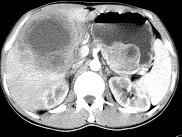

问题 女,61岁,上腹部疼痛1个月,食欲减退,消瘦,CT所见如图,最可能的诊断是()

选项 A.肝脓肿 B.肝转移瘤 C.胃癌肝转移 D.肝包虫病 E.原发性肝癌

答案 C